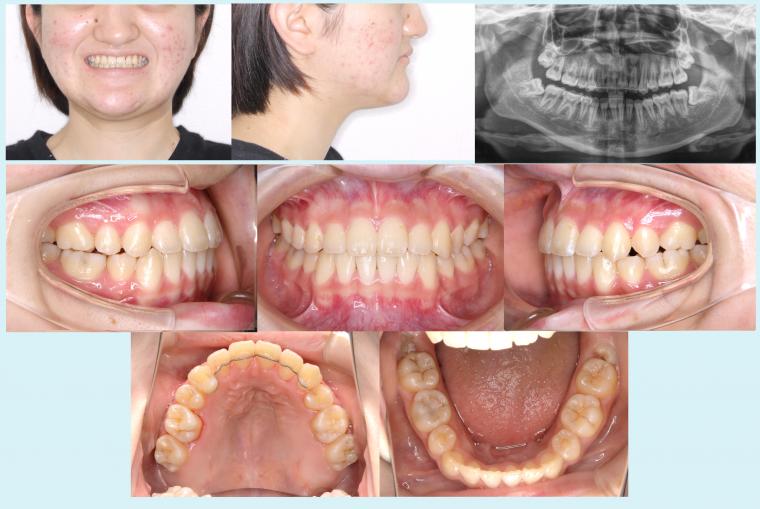

#44 上顎歯列の狭窄を伴う叢生症例